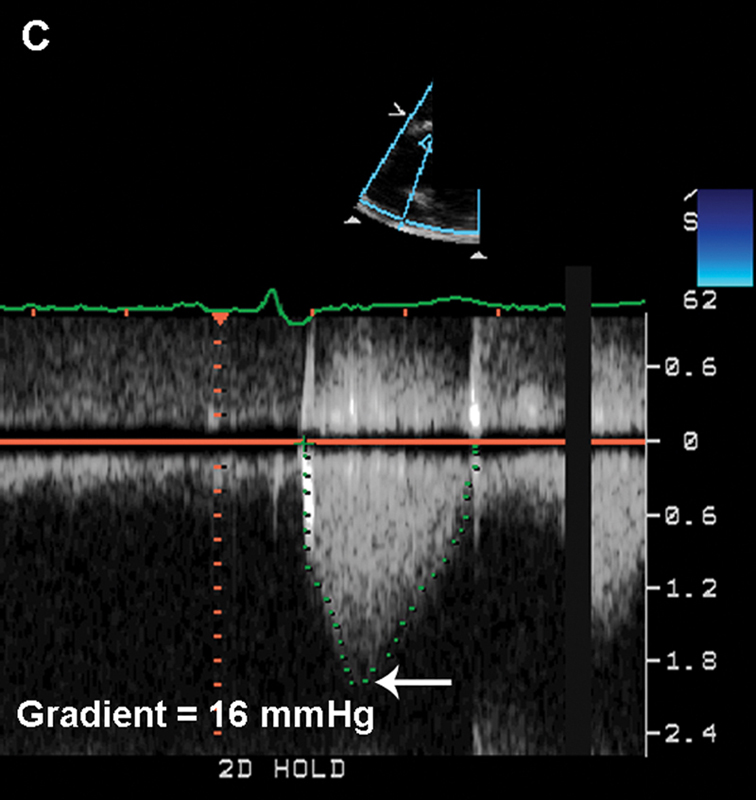

فحوصات تشخيصية لبعض امراض القلب والشرايين التاجية